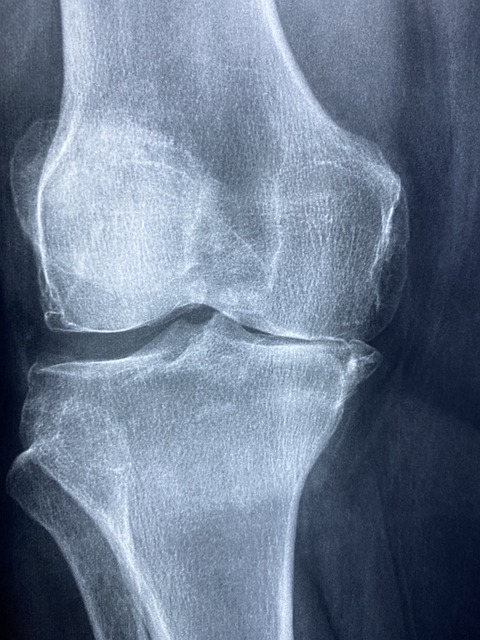

골관절염은 관절의 연골이 마모되어 발생하는 퇴행성 질환으로, 주로 무릎, 손, 엉덩이, 척추 관절에서 발생하며, 통증, 부종, 운동 범위 감소 등의 증상을 유발합니다. 콘드로이친은 이러한 골관절염의 증상을 완화하는 데 도움을 줄 수 있는 것으로 알려져 있습니다.

연구에 따르면, 콘드로이친을 정기적으로 섭취한 환자들은 통증 감소와 함께 관절의 유연성이 개선되었다고 보고합니다. 이는 콘드로이친이 연골 조직을 보호하고, 연골의 손상을 줄이며, 연골 내의 수분 및 영양소 보유 능력을 향상하기 때문으로 해석됩니다.

더욱이, 콘드로이친은 관절염의 진행을 늦추는 데에도 긍정적인 영향을 미칠 수 있음을 시사하는 연구 결과가 있습니다. 이는 장기적으로 관절의 건강을 유지하고, 추가적인 관절 손상을 방지하는 데 중요할 수 있습니다.